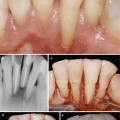

Fig. 5.8

Case II (a–l) Esthetical clinical crown lengthening of maxillary anterior segment. Baseline – gingiva–anatomic crown relationship type I (a, b). Osseous contour before osteotomy and osteoplasty procedures (c). Alveolar crest–cementoenamel junction relationship subtype B (d). Osseous contour after osteotomy and osteoplasty procedures (e). Change of alveolar crest–cementoenamel junction relationship to subtype A (f). Two weeks follow-up – immediately after suture removal (g). Three months follow-up (h). Baseline smile appearance (i). Final smile appearance (j). Gingival anatomy adjacent to upper incisors at 4 months follow-up (k), 4 months follow-up (l)